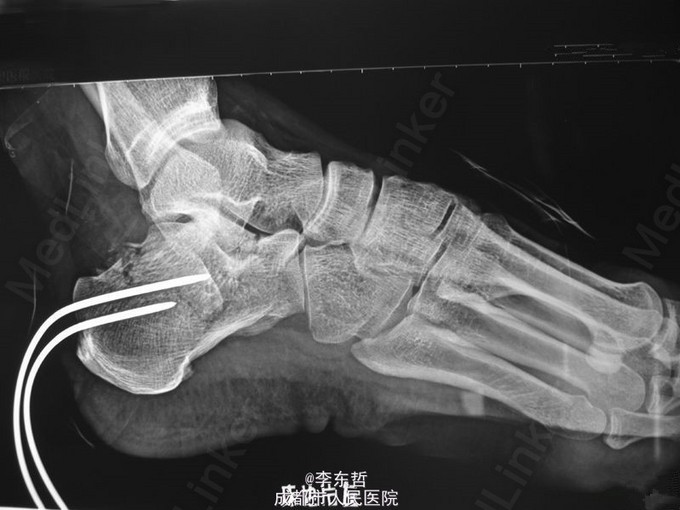

左足跟骨骨折

跟骨骨折

患者男性,60岁;高处坠落致左跟部肿痛10天入院,查体示左跟部略肿,压痛,无皮裂出血;予刚针撬拨术复位。